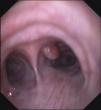

Varón de 76 años sin hábitos tóxicos, trabajador en minería de carbón. Como antecedentes destacan una pleuritis izquierda en su juventud, hipertensión arterial y diabetes; sin antecedentes familiares de interés. Remitido a neumología por expectoración de sangre roja desde hace días, precedida de tos en número 4-5/día. Sin fiebre, dolor torácico, disnea, síntomas extratorácicos, pérdida de peso ni hematuria. Exploración: buen estado general, con leve disminución del murmullo vesicular en hemitórax izquierdo sin adenopatías ni masas. En la analítica destaca glucosa=125mg/dl y microhematuria. Valores funcionales respiratorios normales. La Rx de tórax mostraba ateromatosis aórtica y paquipleuritis calcificada izquierda. La TC toraco-abdominal muestra una lesión nodular de 7mm intraluminal en la porción inicial del bronquio principal derecho (BPD) y lesión expansiva heterogénea de 6,6cm en polo renal derecho, y otra similar en el polo inferior de 3,7cm. En el polo superior del riñón izquierdo otra lesión de 2,6cm. Se realizó fibrobroncoscopia encontrando 2 lesiones polipoideas vascularizadas, una en la cara anterior del BPD (fig. 1) y otra a la entrada del bronquio lobar inferior derecho. Las biopsias se informan como metástasis de carcinoma de células claras. Citologías de orina negativas para malignidad. Debido a la extensión de la enfermedad, no se plantearon medidas diagnósticas sobre las masas renales y se remitió a oncología para valorar tratamiento.

Este caso reúne varias condiciones poco habituales: la hemoptisis lleva al diagnóstico del tumor primitivo renal, que tiene la peculiaridad de presentarse como 3 tumores sincrónicos bilaterales. La TC torácica, con poca sensibilidad para detectar las metástasis, pudo localizar una de ellas, aunque la FB con biopsia bronquial fue decisiva en el diagnóstico definitivo. La ausencia de antecedentes familiares y la edad sugieren tumores renales esporádicos.